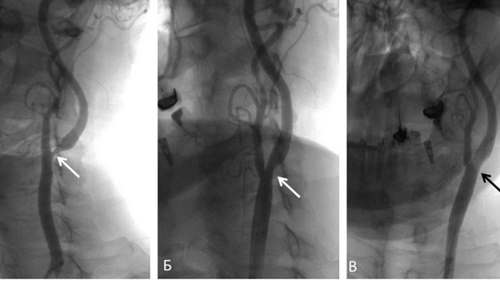

- ангиография с контрастом, необходимая для визуализации состояния кровеносных сосудов, особенно их стенок;

При осложненном вертебро-базилярной недостаточностью шейном остеохондрозе проводится тромболитическая терапия или другие хирургические операции. Для определения состояния позвоночных артерий, установления операционного поля пациенту показана рентгеновская панангография. Вертеброгенное влияние на позвоночную артерию также подтверждается рентгенологическим исследованием, выполненным с функциональными пробами. Биохимические анализы крови проводятся для оценки общего состояния здоровья, выявления неустановленных хронических метаболических или эндокринных патологий.